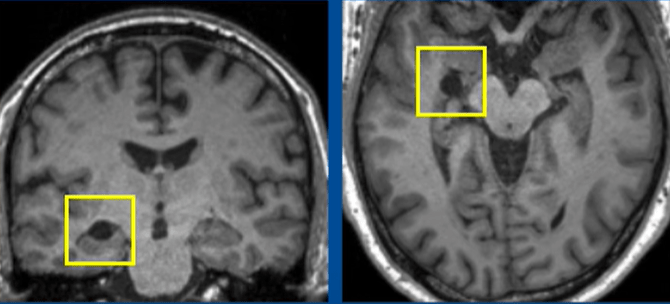

醫生后來發現他的腦部出現一個大小約1厘米的圓形病灶,神經科醫生推測病灶可能是左側海馬回的蛛網膜囊腫,其后診斷他患有罕見的神經系統疾病臉部變形癥(Prosopometamorphopsia,PMO)。

醫生其后發現他的腦部出現圓形病灶。(《The Lancet》圖片)

▲醫生其后發現他的腦部出現圓形病灶。(《The Lancet》圖片)